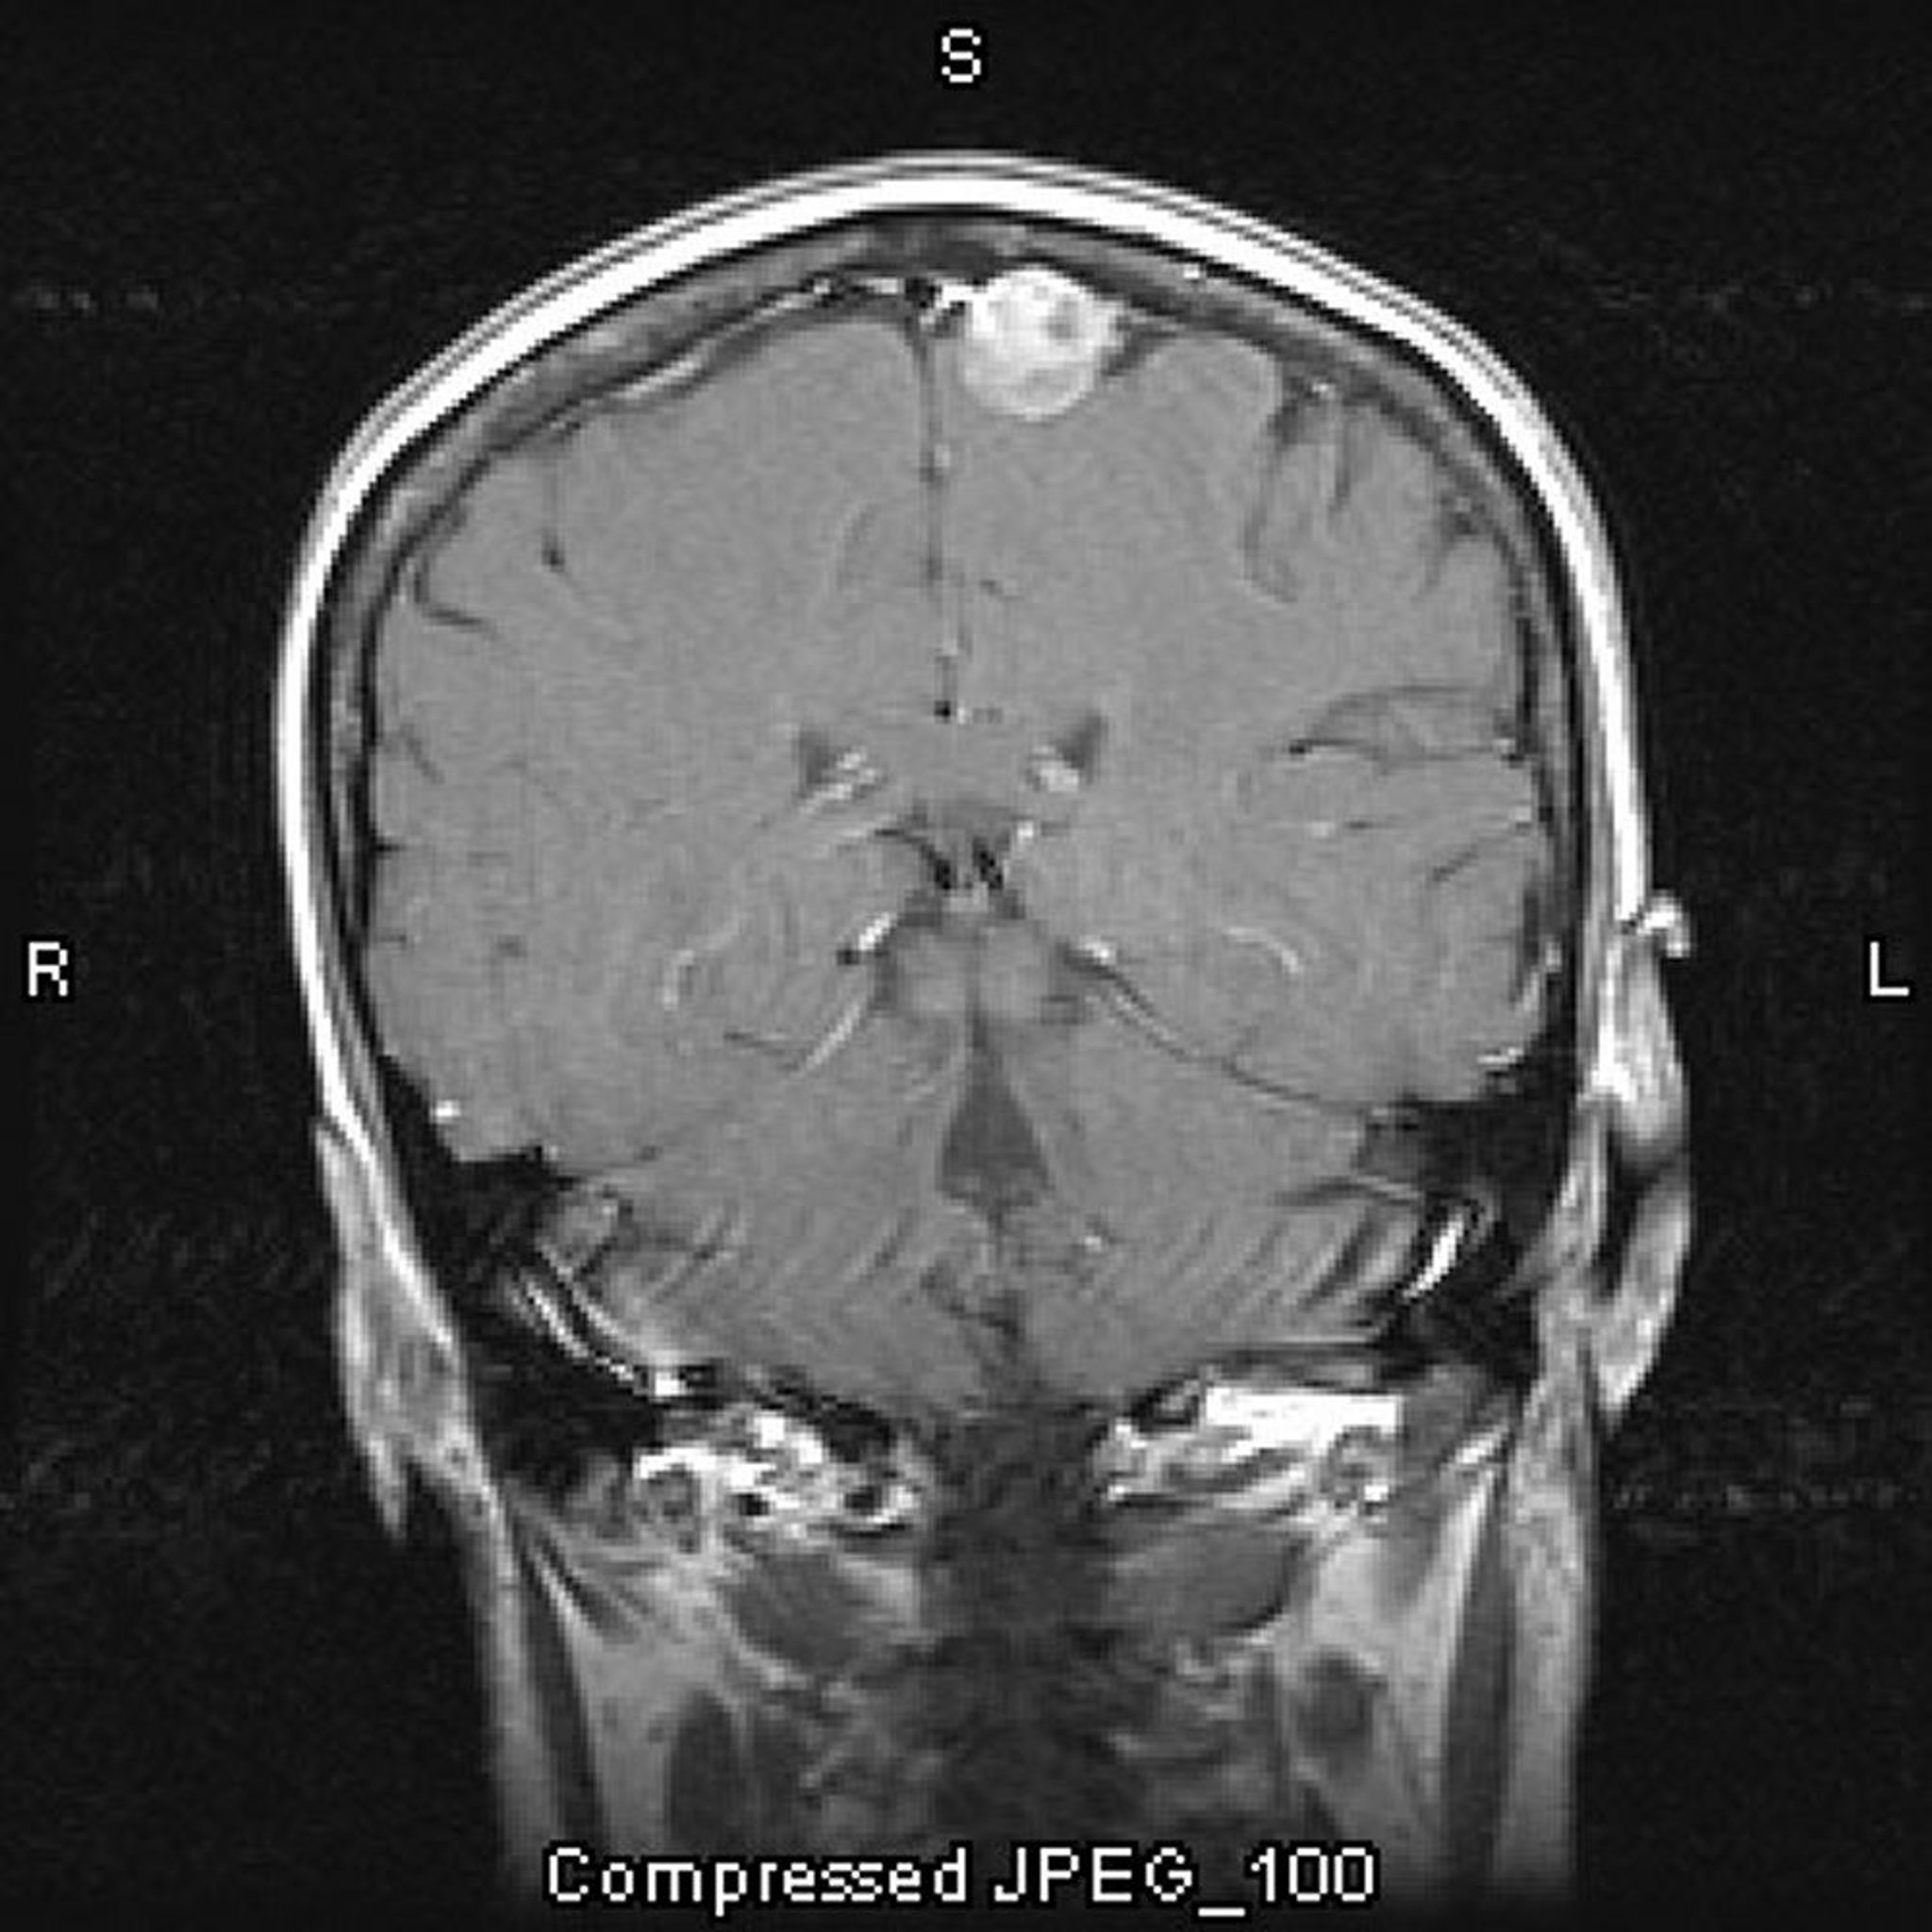

U màng não, cận đường dọc giữa

Hình ảnh chụp MRI có ngấm thuốc cản quang này cho thấy một u màng não. Vị trí cận đường dọc giữa là một vị trí điển hình với u màng não.

Hình ảnh do bác sĩ William R. Shapiro cung cấp